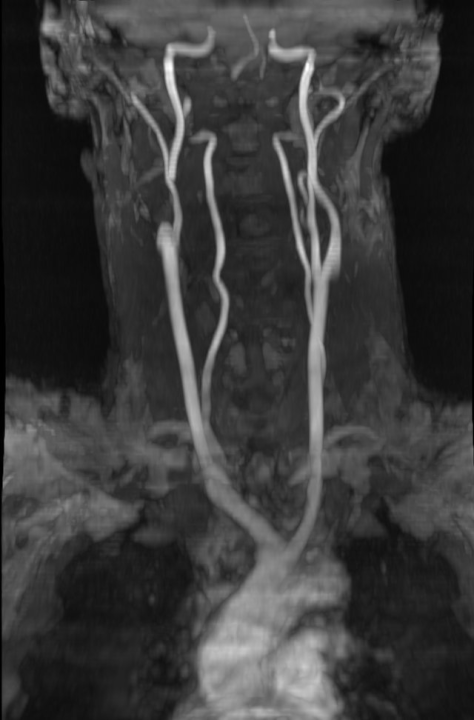

Svjetski dan zdravlja: Ateroskleroza svjetski ubojica broj jedan

Povodom svjetskog dana zdravlja o aterosklerozi kao najvećim javnozdravstvenim problemom i vodećim uzrokom bolesti i smrti na svijetu, pričali smo s doktorom specijalistom neurologije dr.